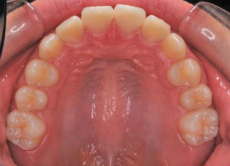

上下あご共にすべての乳歯が永久歯に交換して数か月後の噛み合わせの状態です。

この時点では上あごの12才臼歯である第二大臼歯がまだ生えていません。つまり、歯並びが整ったこの時点で ”もういいですよ” と治療をとっとと終わらせてしまうのはまだ早い ということです。

6才臼歯の後ろに生えてくる予定の12才臼歯がこの時点ではどのように生えてくるかがわからないからです。

従って、12才臼歯が下あごの12才臼歯と適度にきちんと咬みあうことが確認できるまでせめて経過観察をします。